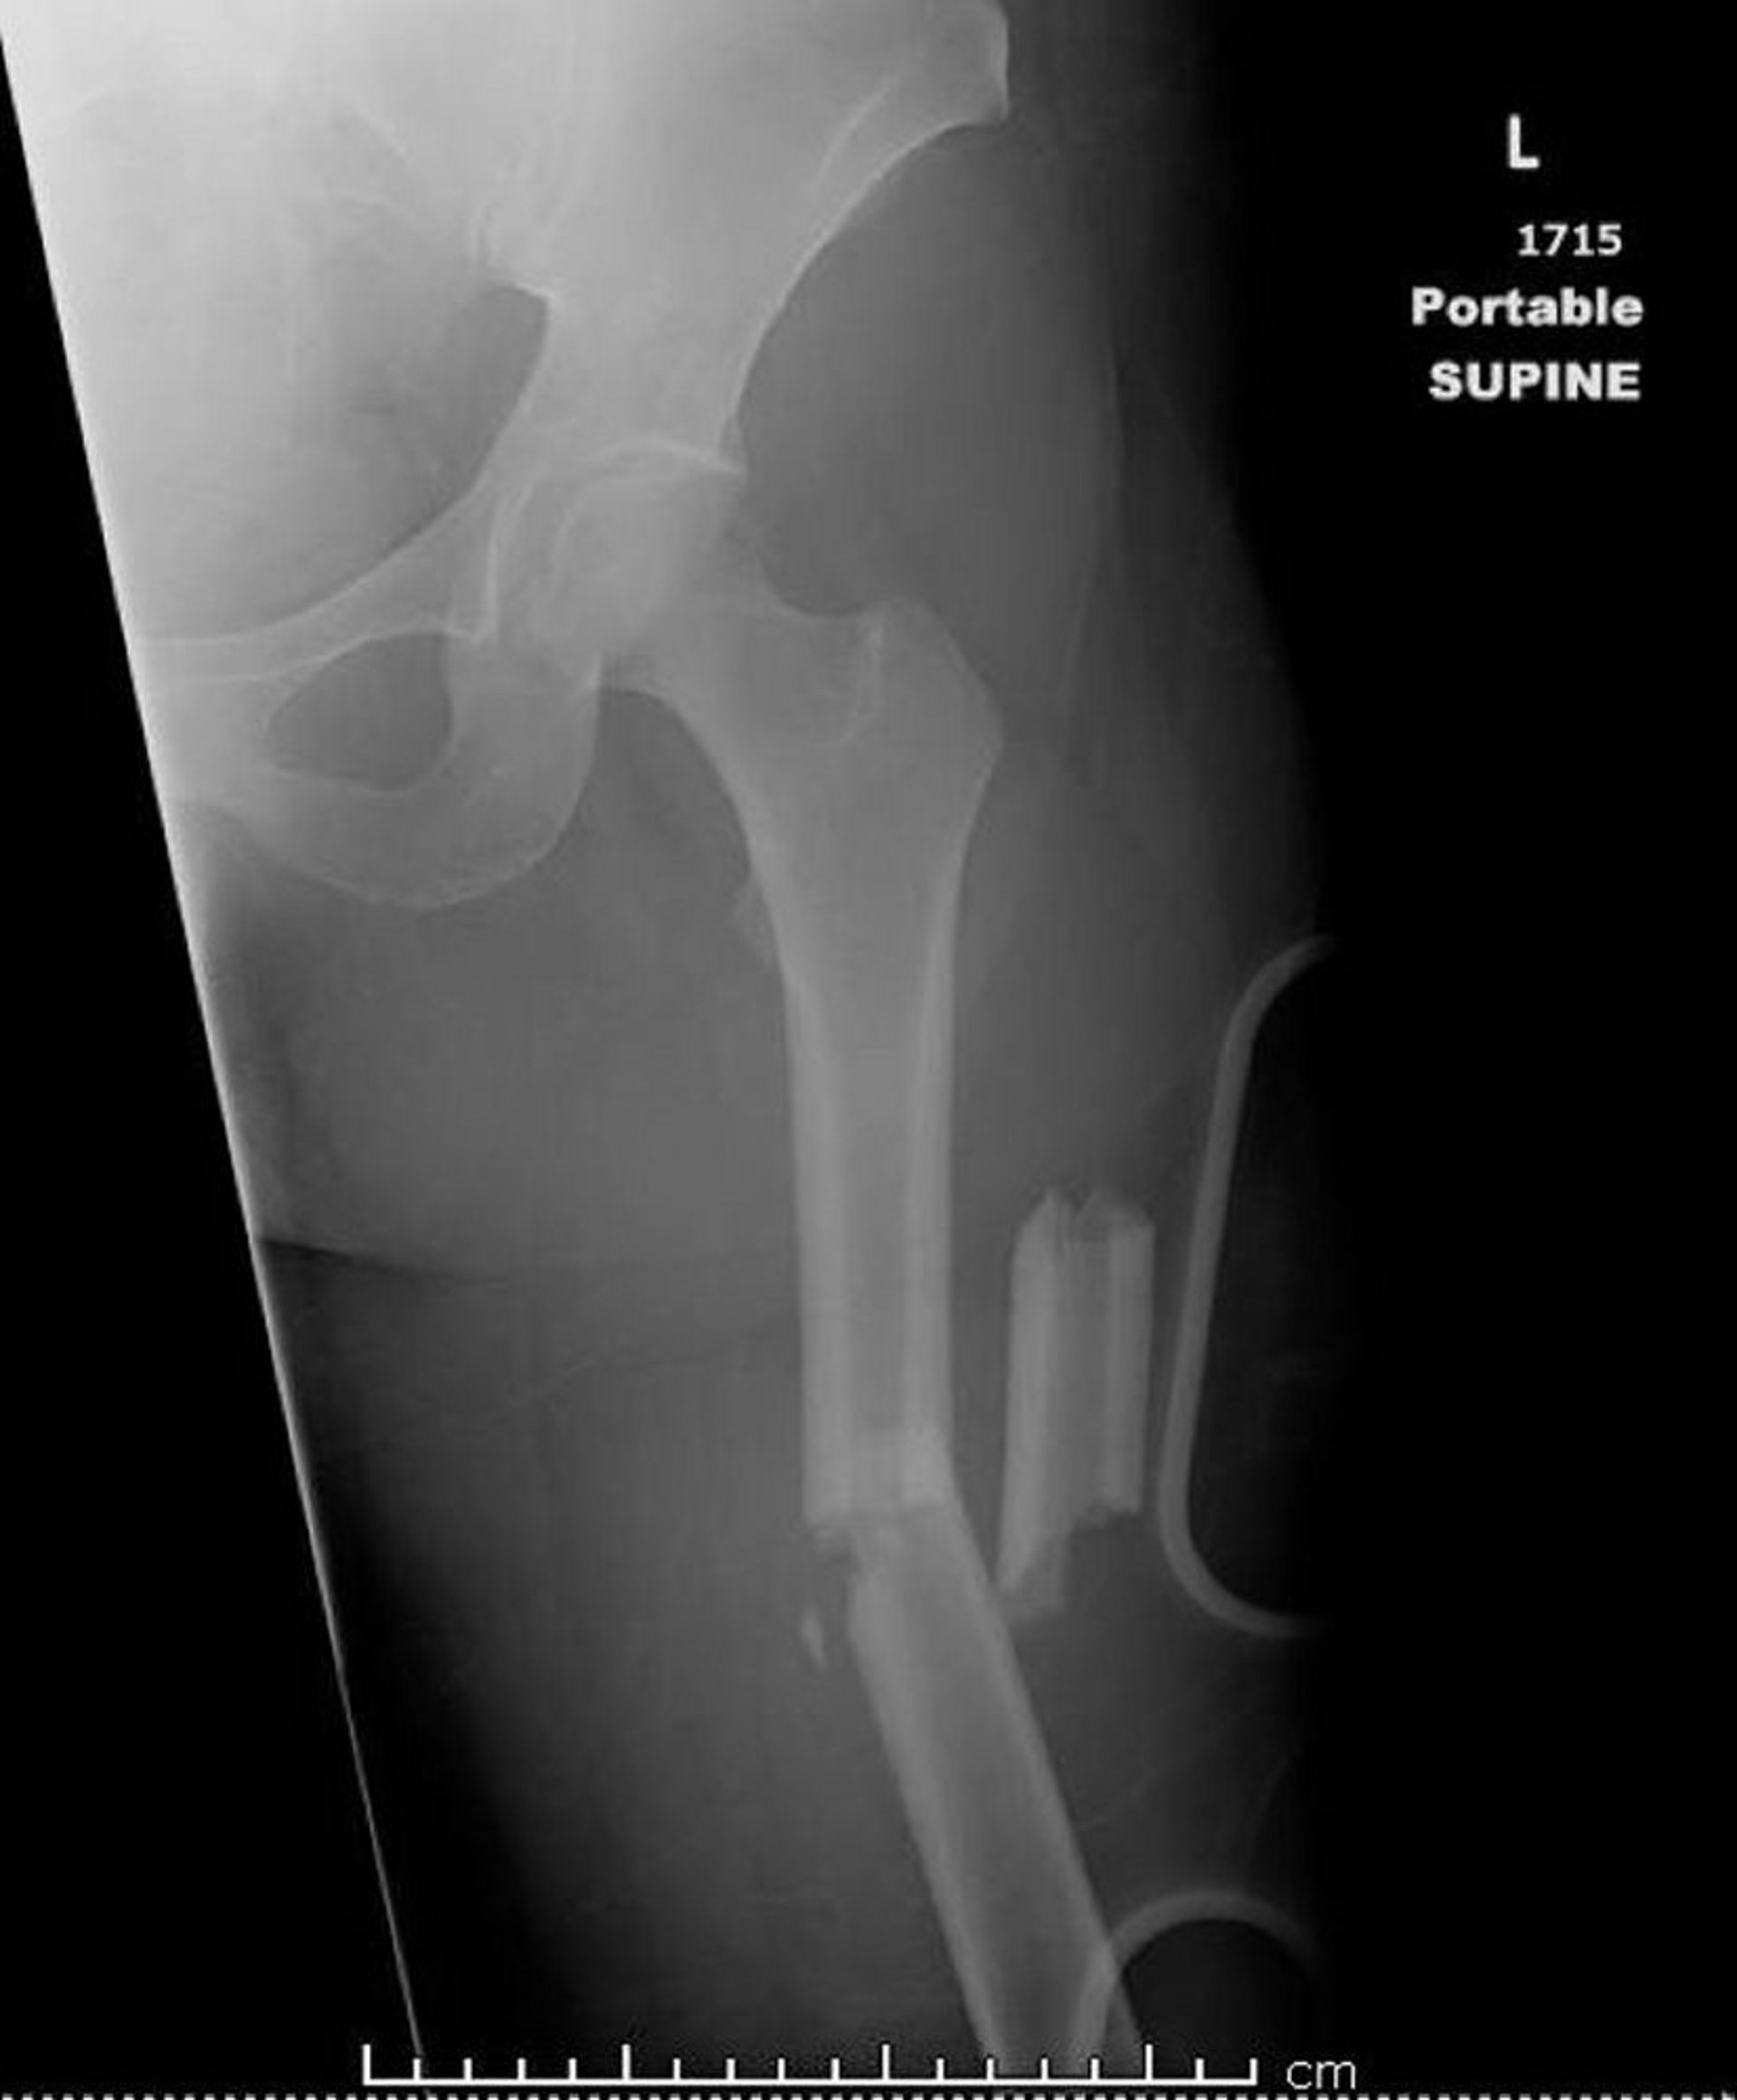

Esta imagen muestra una fractura conminuta angulada del tercio medio de la diáfisis femoral, que está acortada.

Image courtesy of Danielle Campagne, MD.